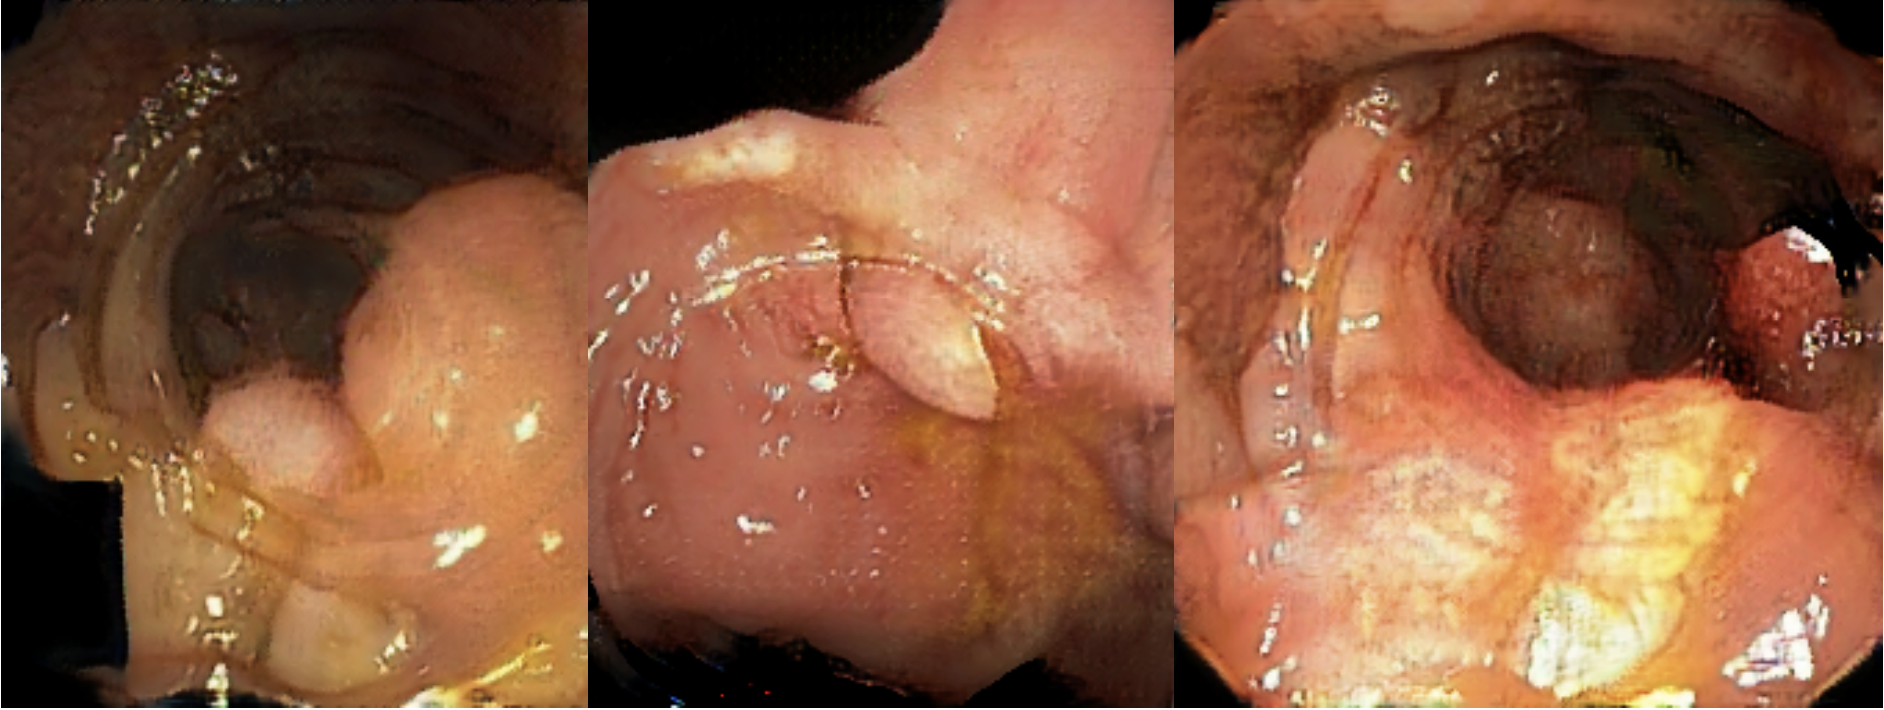

Test data: Kvasir-SEG

• 1000 images

• various sizes

• Each image contains 1 polyp

• Collected and annotated by medical professionals

Jha, Debesh, et al. "Kvasir-seg: A segmented polyp dataset." MultiMedia modeling: 26th international conference, MMM 2020, Daejeon, South Korea, January 5–8, 2020, proceedings, part II 26. Springer International Publishing, 2020.